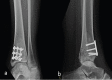

Figure 1

Anteroposterior (a) and oblique (b) radiographs of the left ankle showing a subtle area of osteonecrosis in the distal tibia.

Figure 2

Anteroposterior (a) and oblique (b) radiographs of the right ankle showing no abnormality.